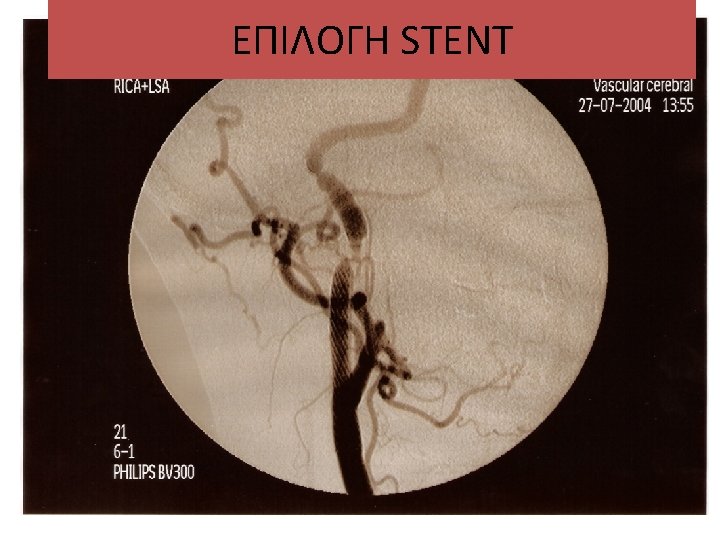

ΕΠΙΛΟΓΗ STENT Carotid angioplasty and stenting

ΕΠΙΛΟΓΗ STENT • • Carotid (self-expandable, braided or nitinol) Vertebral (balloon expandable) Subclavian (balloon expandable) Inominate (balloon expandable) Renal (balloon expandable) Aorta (nitinol, balloon expandable) Common Iliac (balloon expandable, nitinol) Ext. Iliac (nitinol)

Carotid angioplasty and stenting